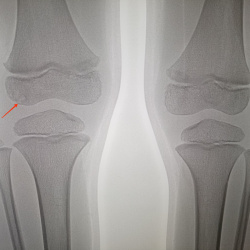

6 лет, жалоб на боль в коленном суставе не предъявляет, травм не было, что за участки просветления в области эпифиза?